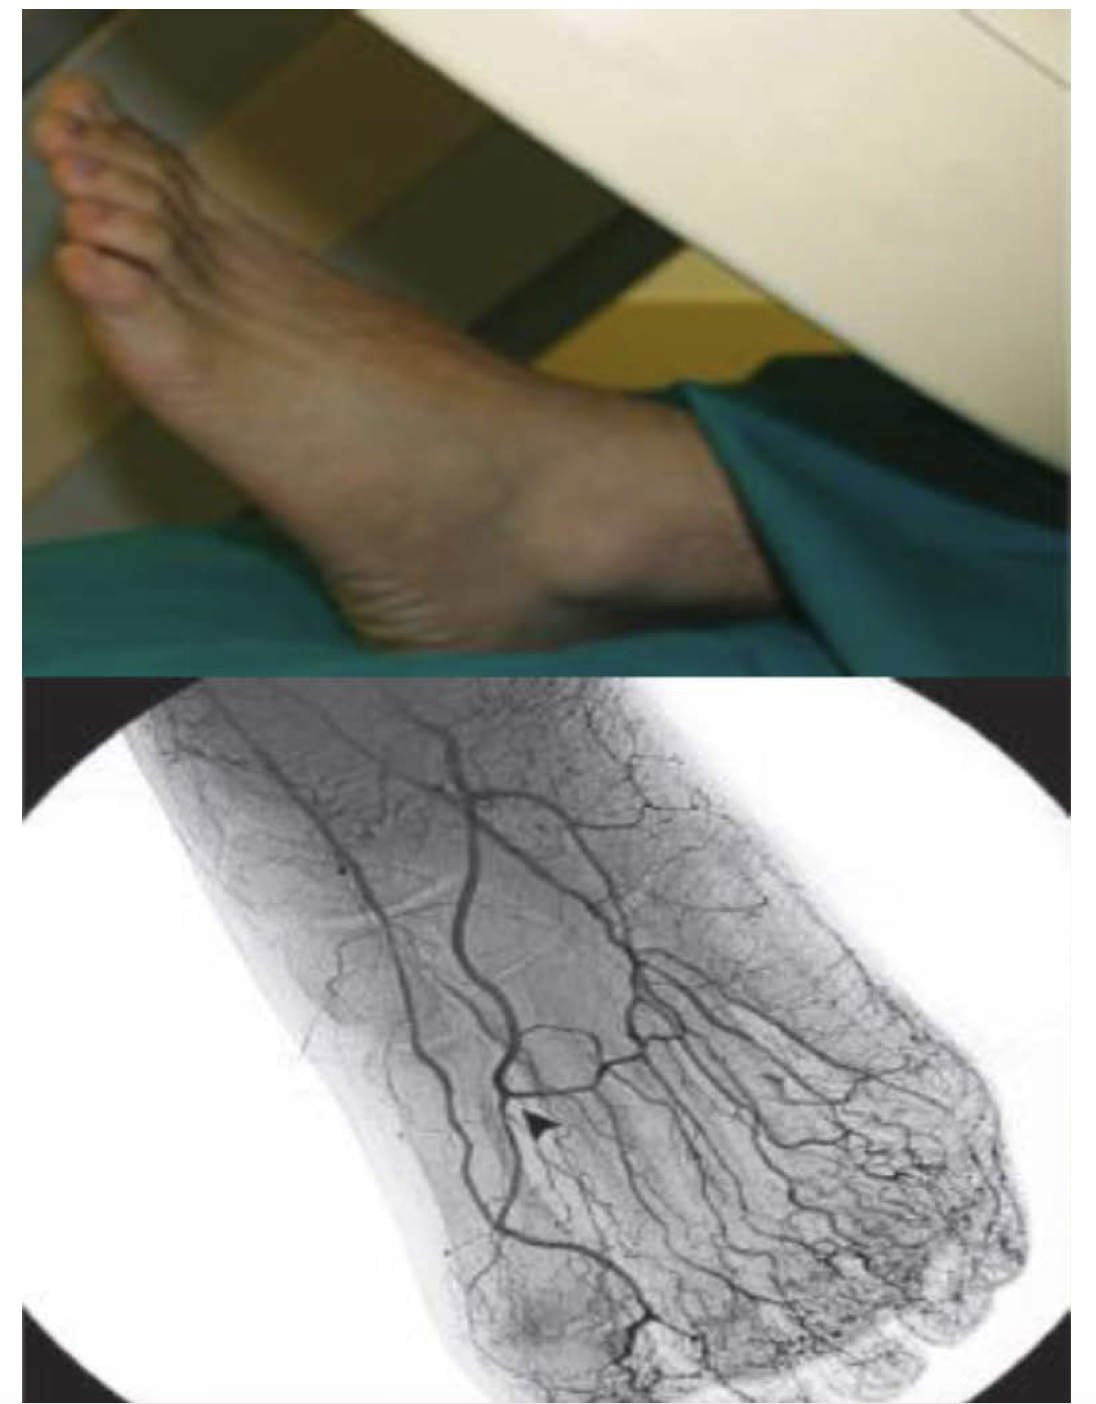

Upon angiographic evaluation, we can assess the pedal arch disease burden and further classify it based on the patency of the anterior or posterior circulation.13 Two views should be performed in all cases using digital subtraction angiography with prolonged imaging to allow late collateral filling. In the lateral oblique view, the fifth metatarsal bone must be separated to properly visualize the common plantar artery and its bifurcation, the dorsalis pedis, and its connection to the pedal arch via the deep perforating artery (Figure 1).21 The anterior-posterior view is also required to visualize the anterior pedal arch vessels directly and evaluate the distal branches into the foot and toes.21 This is essential for visualization of the transmetatarsal artery access required for access in complex cases of CLTI (Figure 2).22

After angiograms are obtained, the pedal arch can be classified into several types. Type 1 has both dorsalis pedis and plantar arteries patent. Type 2A has only a dorsalis pedis artery patent. In type 2B, only the plantar artery is patent. In Type 3, both dorsalis pedis and plantar arteries are occluded.13

In Figure 5 and Figure 6 we illustrate a case where PAR was performed and the arch was utilized for a retrograde crossing of a flush occlusion of the posterior tibial artery. The patient in our case was referred for CLTI with nonhealing wounds in the toes and heel. The anterior tibial artery was recanalized during the initial procedure using laser atherectomy and angioplasty. Then using an antegrade approach, the anterior tibial artery was wired into the dorsalis pedis, across the arch, and retrograde up the posterior tibial artery into the tibioperoneal trunk and externalized in the popliteal artery. This allowed for recanalization of the anterior and posterior tibial artery with a complete plantar arch on the final angiogram, leading to wound healing.